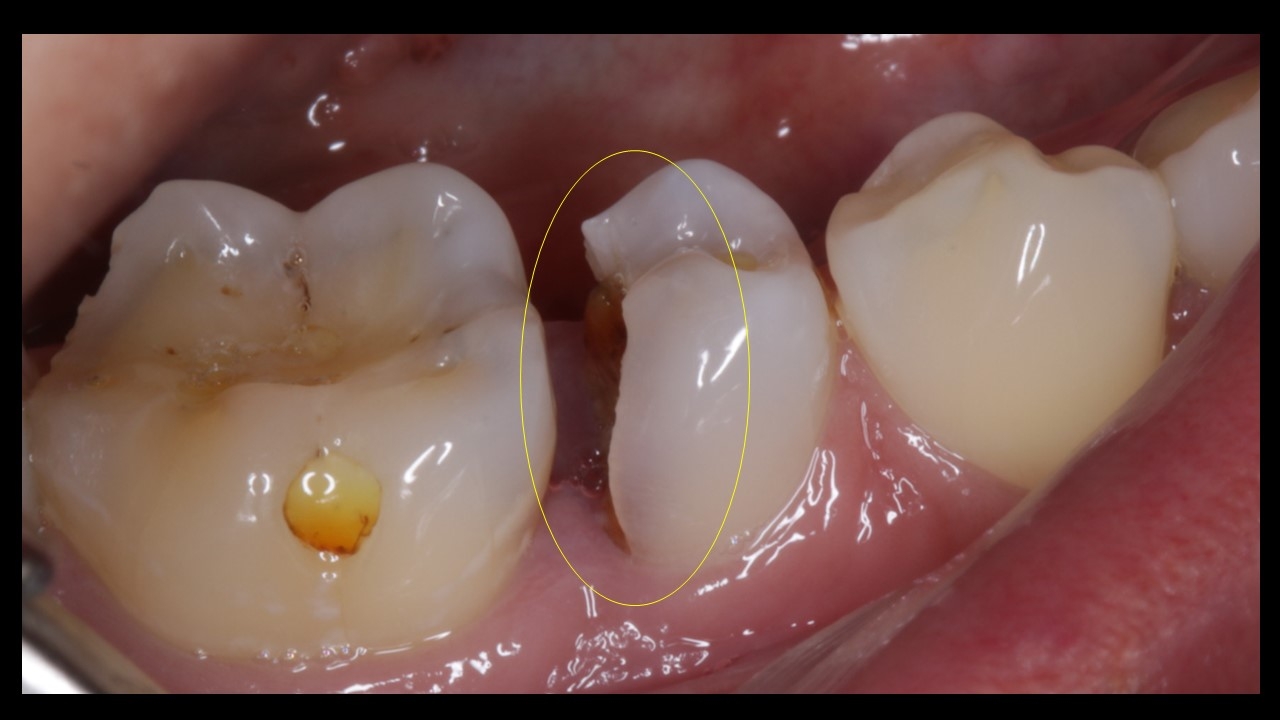

Patient presented with pain and discomfort in the lower right second premolar. Pain was of radiating type accompanied with food lodgement. On examination, the lower right 2nd premoalr was decayed with a portion of the distal surface lost due to the process of deacy. Examination alos revealed decay of the molar on the mesial side. Typical presentation that accompanies food lodgement and decay.

Incidentally the 1st molar on the left side was also decayed , with pulpal invovement requiring intervention.